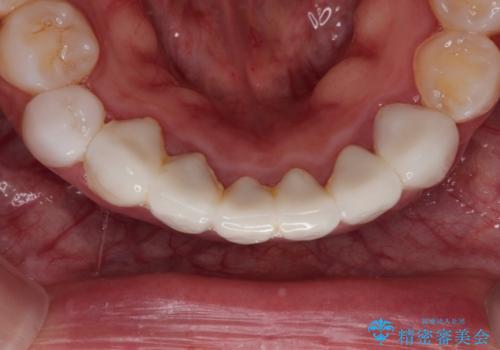

【オールセラミック】下の前歯が痛い。

- 以前に治療した前歯が痛むことを主訴に来院されました。

根っこに病気があり、根管治療から被せ物まで治療を行いました。

根管治療を行った後、3ヶ月間治癒の確認をしてからオールセラミックスペシャルで治療を行いました。